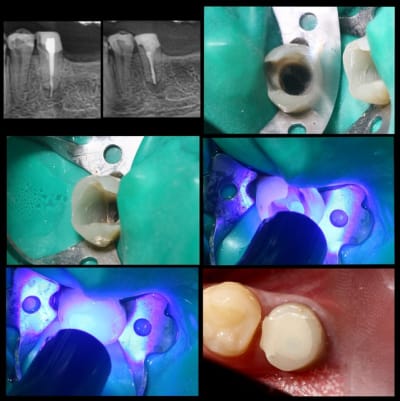

Pour exposer mes propos, cas de ce matin.

Endo galère à reprendre, reconstruction compo pré endo.

Une fois l'endo terminée, j'agrandi ma cavité pour ne garder en périphérie que l'épaisseur de la futur céram.

Je fais ensuite mon protocole adhésif avec tenon fibré.

A la dépose il reste à préparer, le compo pré endo sera tout retiré... ne restera que la dentine et le SC33.

C' est un cas un peu extreme, mais le pronostic serait encore pire avec un Fx moignon... longueur de racine 10mm...

Inlay réalisable sur 24 et 34 ?

Est-ce que le collage suffirait à maintenir les parois ?

Le choix thérapeutique pris a été très classique.

Arnaud Go écrivait:

> Onlay réalisable sur 24 et 34 ?

oui

> Est-ce que le collage suffira à maintenir les parois ?

non, je préférai les recouvrir sur 1.5 mm par l'onlay